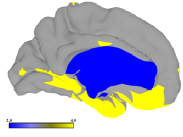

3.3 Methods Comparison

Figure 5 presents the L1 norm of B and C obtained for all our algorithm and datasets. Ten steps of refinement were conducted. At each step, five faces were subdivided and the algorithms run for ten optimization steps. Our results suggest that the tradeoff between the sparsity of B and C is different for the parameters selected. Because projected NMF do not control the sparsity of the loadings, PNMF basis tend to be very sparse but the projected loadings are not. The other factorization schemes balanced the L1 norms of B and C. For the parameters selected, the basis generated by dictionary learning were slightly sparser. We illustrate in figure 6 the results obtained when decomposing the myelin data using LE-PNNMF for a larger number of iterations. The basis obtained nicely decompose the map of large data variability into weakly overlapping components. The refinement had focused accordingly.